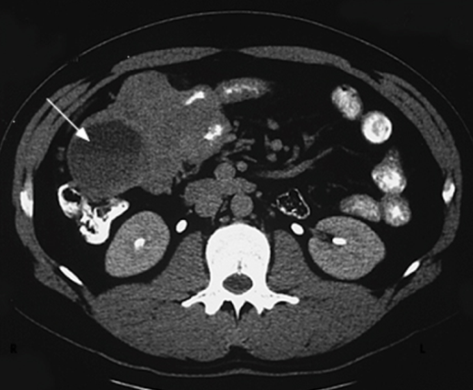

OBB-ın atreziyası və stenozu yuxarı bağırsaq keçməzliyi əlamətləri ilə təzahür edir. Rh-ji olaraq OBB-ın kəskin genişlənməsi və üfiqi maye səviyyələri müəyyən edilir. USM və KT zamanı kəskin genişlənmiş mədənin və OBB-ın konturları görünür.

Uzunmüddətli anamnez, arıqlama, qarında kütlənin əllənməsi, tutmaşəkilli qarın ağrıları, duodenal keçməzliyə bağlı qusma (requrqitasiya) və ektopik mədə mukozasının xoralaşmasına görə qanaxma (qanlı qusma, melena) hadisələri, diaqnostik şübhə əlamətləridir. Əksər xəstələrdə Rh-ji müayinə hesabına diaqnoz qoyulmur. Şübhəli hadisələrdə kontrastlı KT, MRT və laparoskopiya müayinələrinin rolu böyükdür. Şüa müayinələri zamanı OBB-ın mənfəzinin dolma defektinə görə daralması müəyyən edilir (şək 3. ).

Şək. 3 Onikibarmaq bağırsağın ikiləşməsi (mənfəzin dolma defekti hesabına daralması)